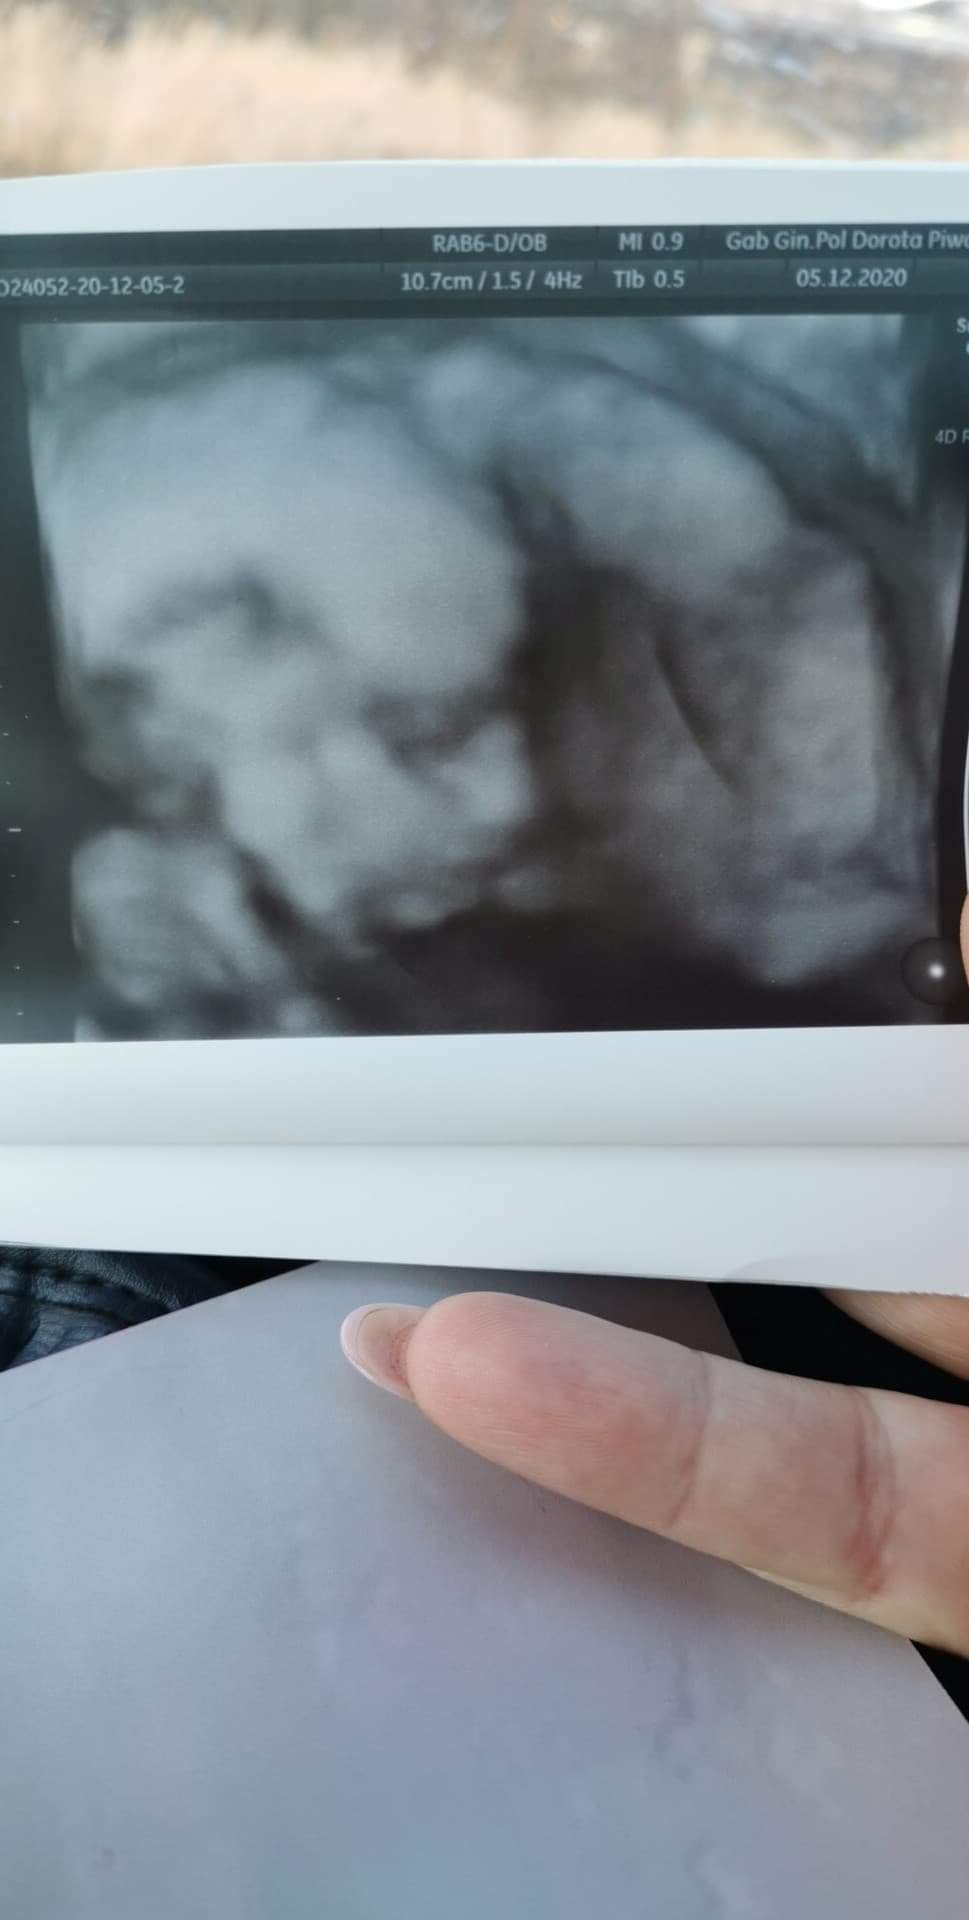

Hej pani doktor dzisiaj potwierdziła i pokazała że jednak będzie synek. Niezła odmiana po dwóch dziewczynach.. Dzisiaj 19+5 mały waży 330 gram i wszystko ok. Lozysko na przedniej ścianie stąd ruchy czuje słabiej. Szyjka ok

Załączniki

• received_183302253449716.jpeg

received_183302253449716.jpeg

58,3 KB · Wyświetleń: 168